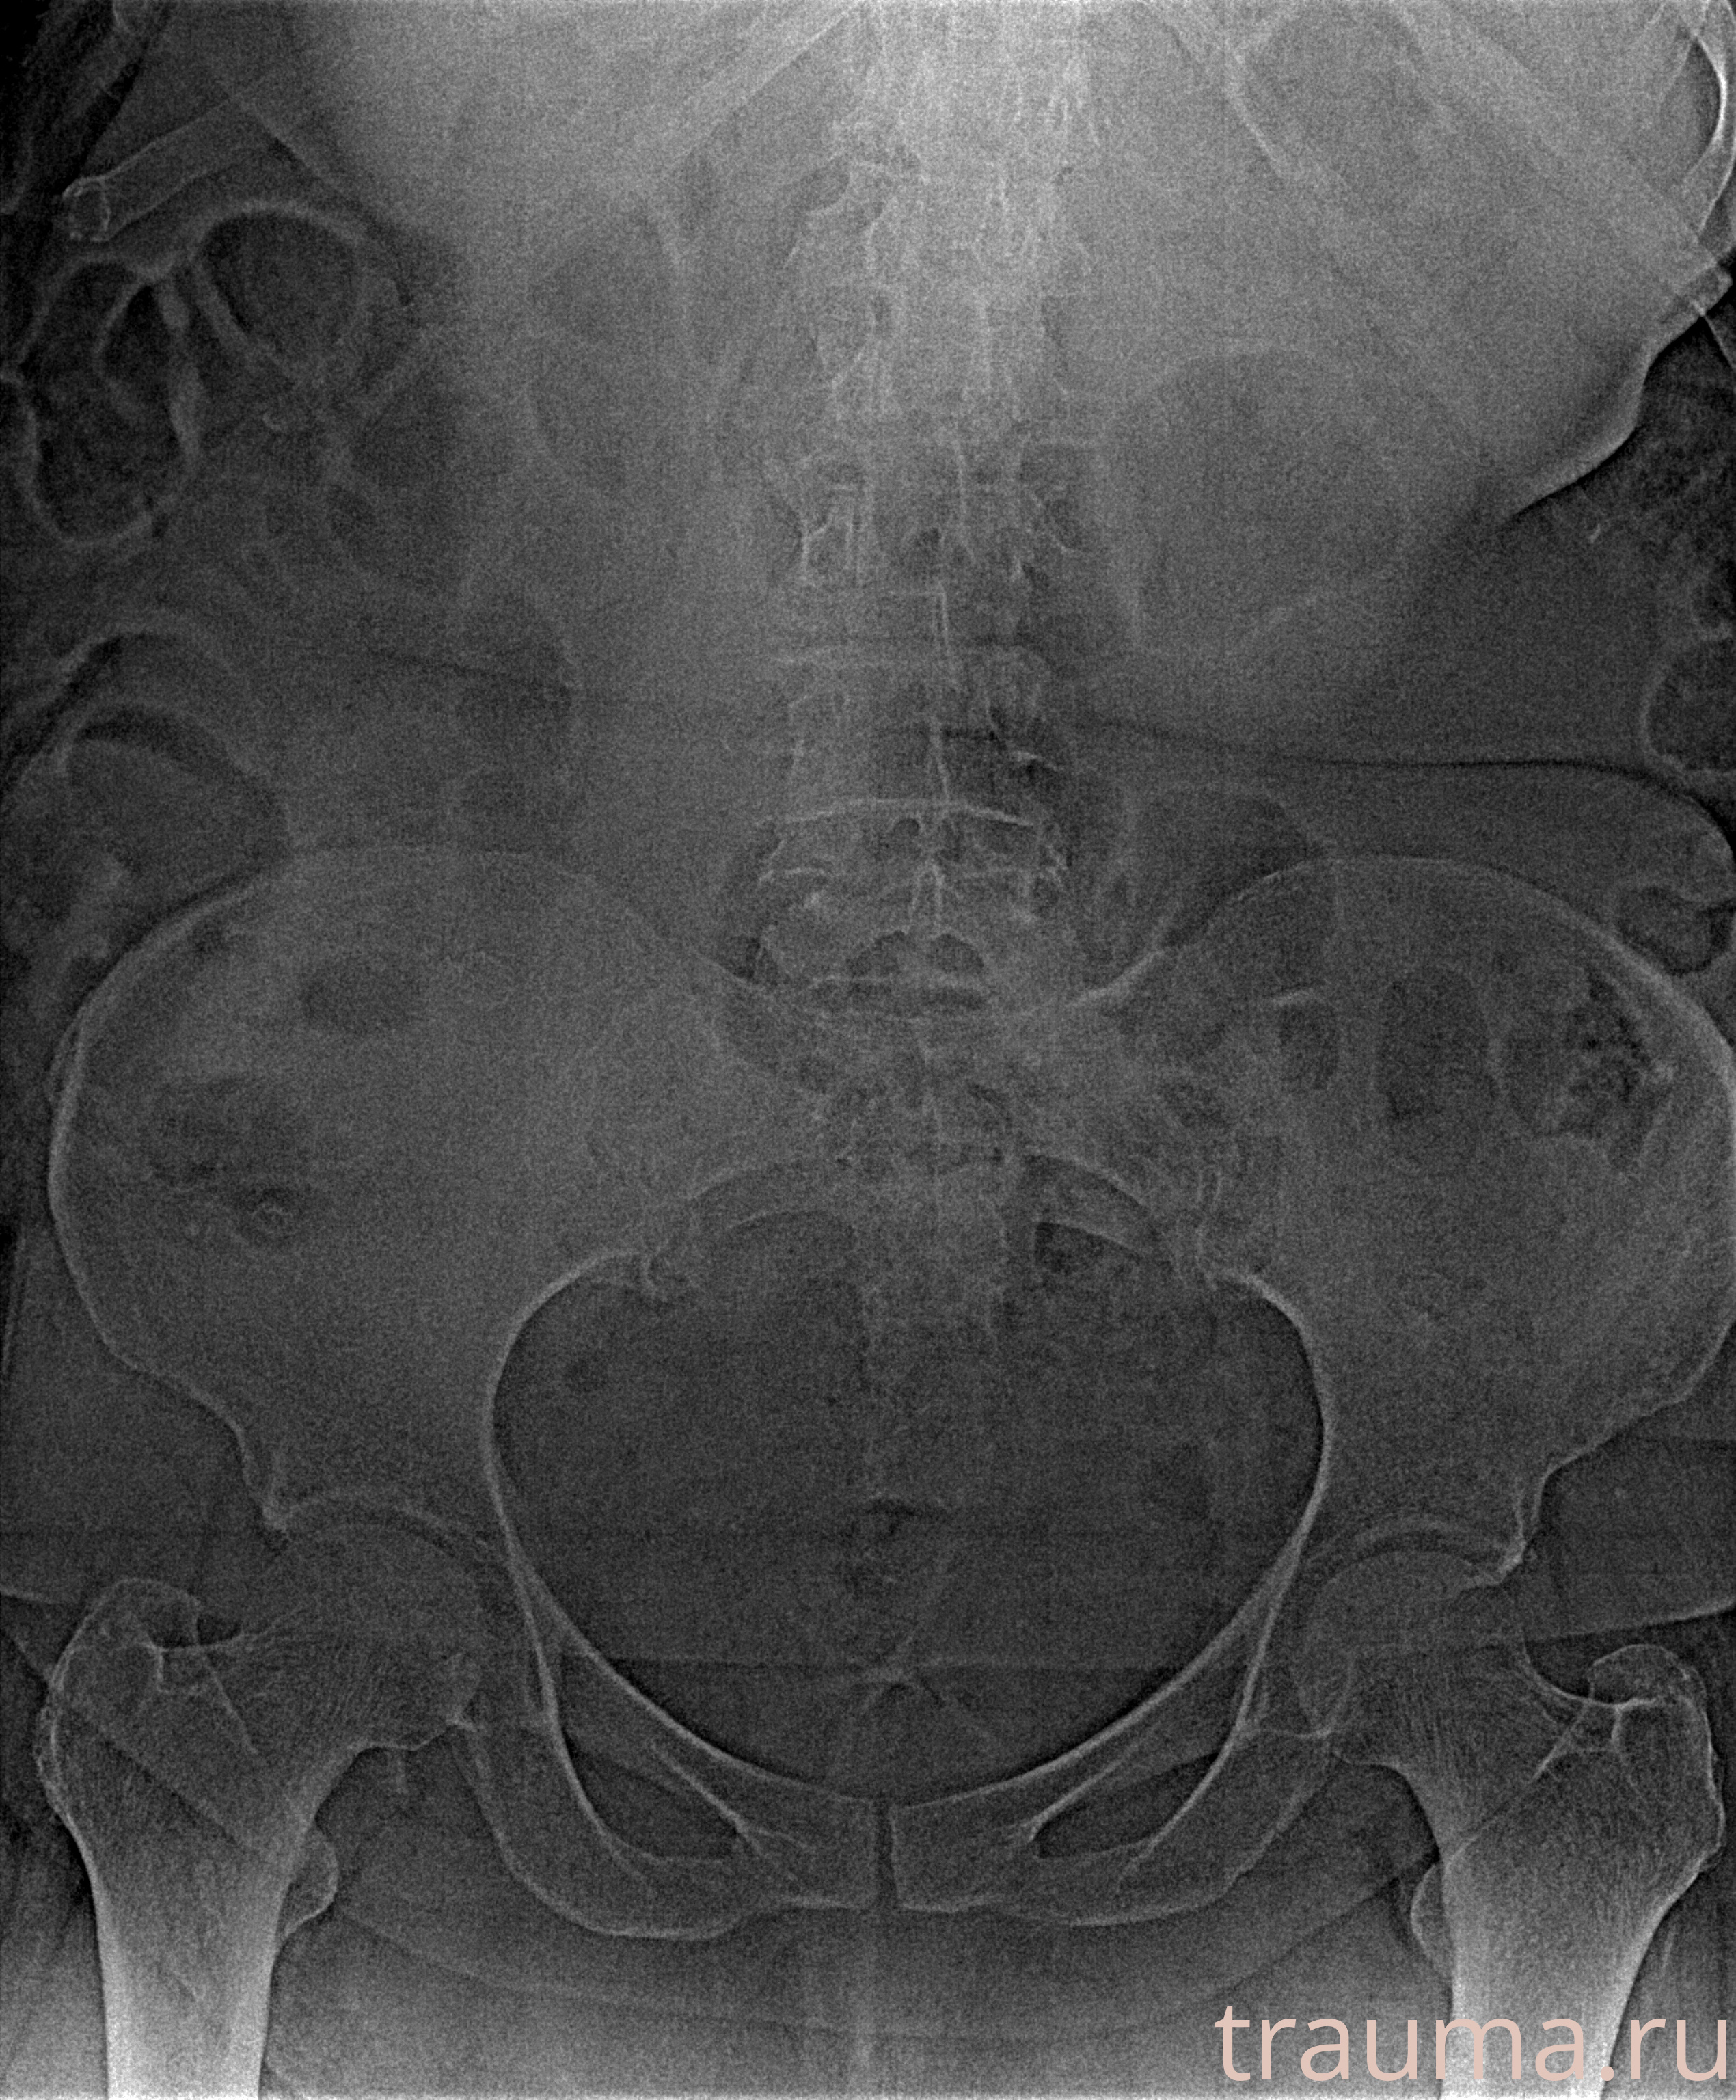

Рентгенограммы

Рентген на дому: по вашему адресу приезжает врач-рентгенолог, травматолог-ортопед с мобильным рентгеновским аппаратом, проводит диагностику травмы или заболевания, делает необходимые рентгенограммы, дает рекомендации по дальнейшему лечению. Получить качественные снимки в домашних условиях возможно благодаря уникальной методике, разработанной МосРентген Центром для института  Склифосовского